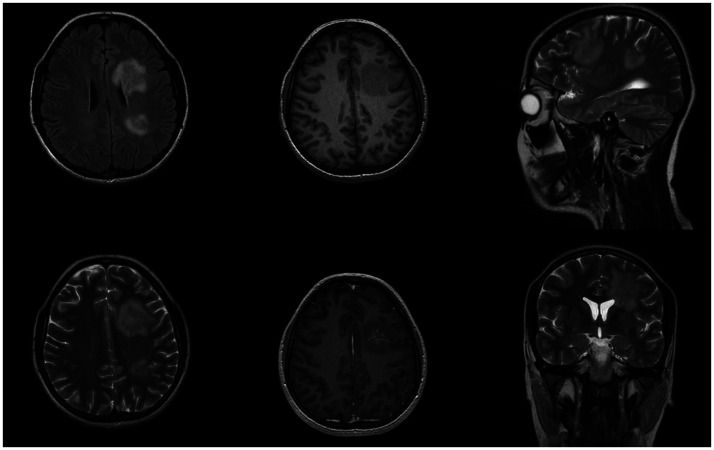

Case: We present a unique case of SLIPPERS observed in a 26-year-old woman with no notable medical or familial background. Laboratory findings ruled out certain diseases from the list of differentials and cranial MRI showed T2 hyperintense areas with linear-patchy enhancements, a pattern consistent with SLIPPERS syndrome. Consequently, patient was diagnosed with SLIPPERS syndrome and received methylprednisolone therapy.